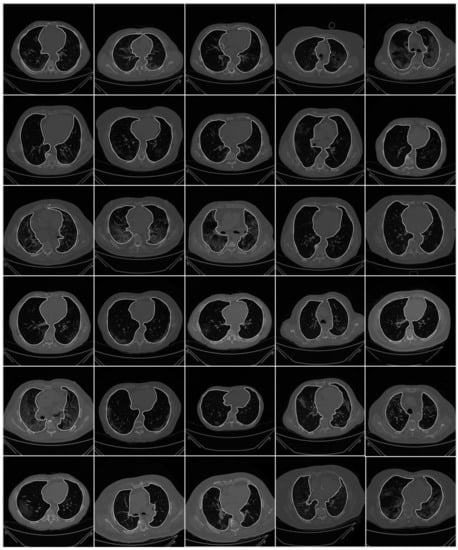

2.1.3. Data Preparation